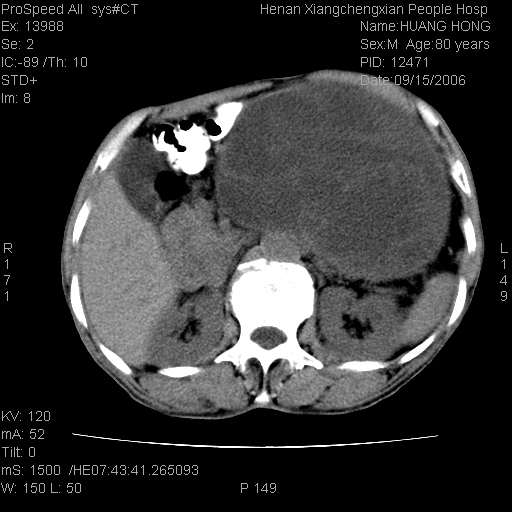

患者, 男, 80岁, 发现上腹部包块1年余,无其它不适.2006-9-14ct片是喝水后扫描2006-9-15ct片没喝水扫描![]() ![]() ![]() ![]() ![]() ![]() ![]() ![]() ![]() ![]() ![]() ![]() ![]() ![]() ![]() ![]() 以上是喝水片 以下是空腹片 ![]() ![]() ![]() ![]() ![]() ![]() ![]() ![]() ![]() ![]() ![]() ![]() ct:胰腺前方、肝脏与胃之间可见巨大类圆形囊性低密度影,大小约152mmx145mmx118mm,上缘平t11椎体上缘,下缘平l3椎体下缘,密度均匀,ct值15hu,其内呈多房分隔,囊壁薄且光滑,边界清晰,周围组织及器官明显受压。肝脏实质内未见异常密度影,胆囊未见异常,胰腺密度未见异常,脾脏大小、形态及密度未见异常,腹膜后间隙未见肿大淋巴结影。 印象:胰腺前方、肝脏与胃之间巨大类圆形囊性低密度影.性质待定。多考虑:.肠系膜巨大囊肿。 守望可可西里发言:支持楼主,考虑肠系膜囊肿,多为小肠系膜。 ysxyy发言:我总觉得这个病人虽然很像肠系膜囊肿,但还是应该强化一下; 下面这几幅图里肿块和主动脉的关系不太清,不知能否除外血管性来源? ![]() ![]() ![]() 病理结果:横结肠系膜间叶瘤.部分区域间质细胞增生活跃. 病理图片 ![]() 良性间叶瘤:是指由两种或两种以上的间叶组织所构成的混合性肿瘤.肿瘤仅发生在腹膜后和肠系膜,.前者较后者多发.良性间叶瘤常发生在肾或四肢,腹膜后较少见,各年龄均可发病.女多与男,预后较好,但术后易复法. 恶性间叶瘤:由两种以上恶性间叶组织成分组成. 光镜:肿瘤由脂肪/血管/平滑肌构成. 原贴地址: http://www.radinet.com.cn/forum_view.asp?forum_id=4&view_id=16217 ok |